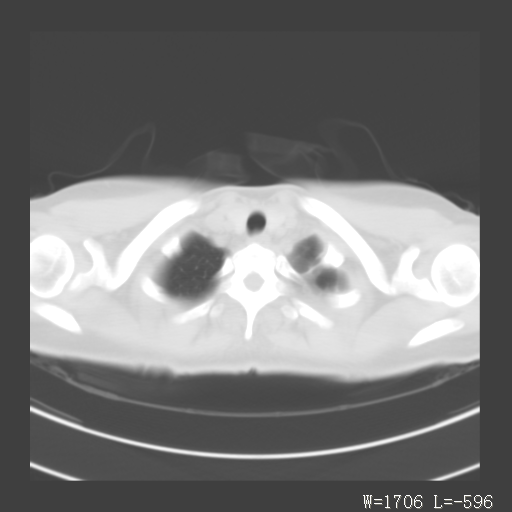

标题: CT27017:1、肺结核?2、永存左上腔静脉。 [打印本页]

标题: CT27017:1、肺结核?2、永存左上腔静脉。

女,32岁,自述肺结核治疗多年复查。